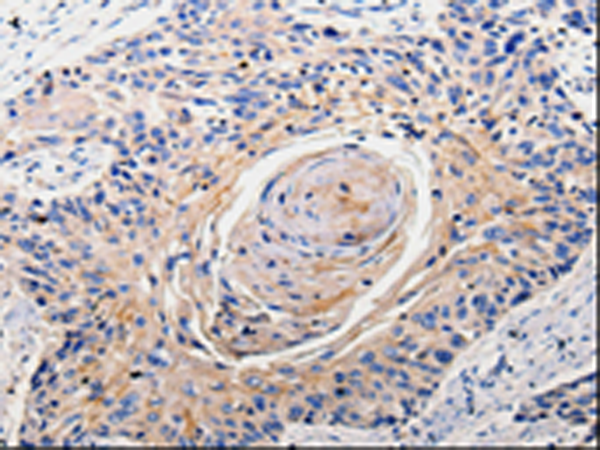

分类: 科研抗体货号: P10624别名: OOMA1; PLEIAD; C5orf25应用: IHC反应种属: Human